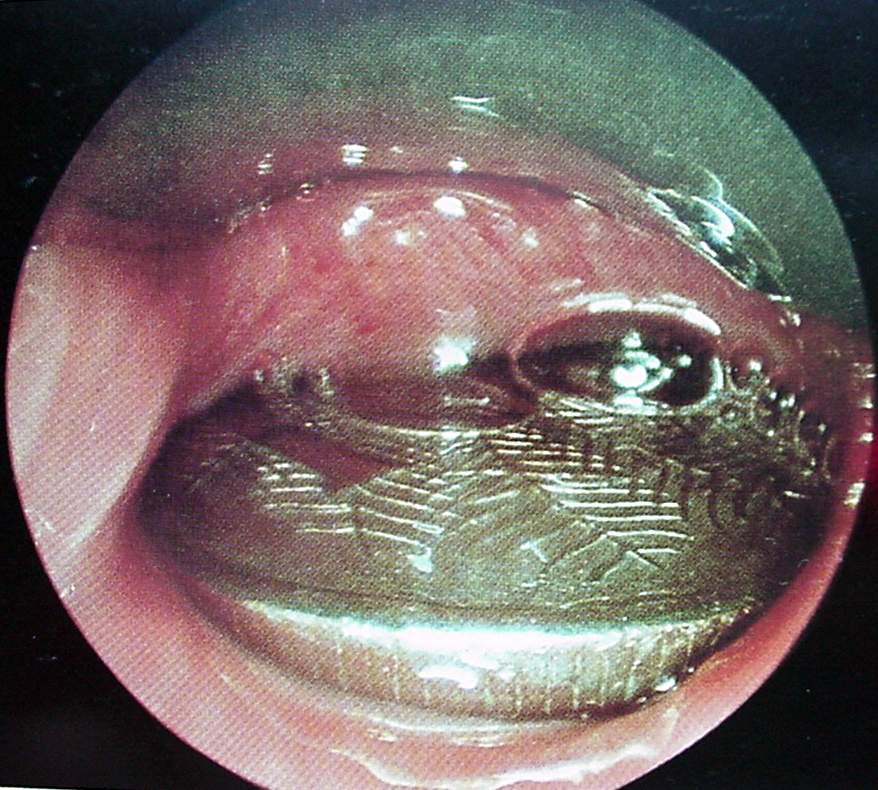

Pharynx and Esophagus Clinical Photos for Static Stations